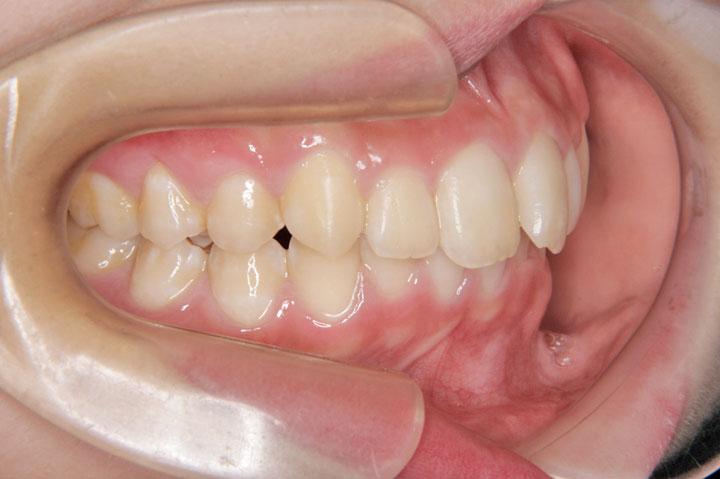

叢生(乱ぐい歯)

上顎前突(出っ歯)

上顎の前突感と前歯のデコボコを主訴に来院された中学1年生の患者さんです。上顎前突と叢生の程度は比較的軽度でしたので、非抜歯でエッジワイズ治療を行っております。顎間ゴムへの協力もよく、プロファイル(側貌)の改善も得られ良好な治療結果となりました